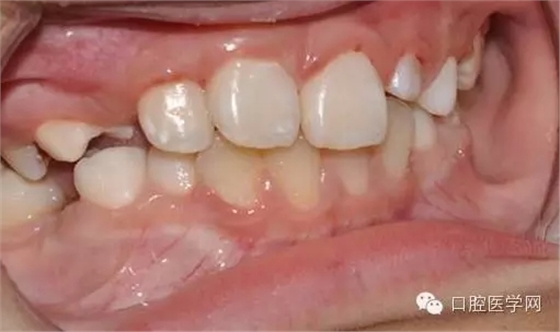

用時(shí)9周完成埋伏牙牽引。

孩子自信的微笑,是我們最大的幸福。